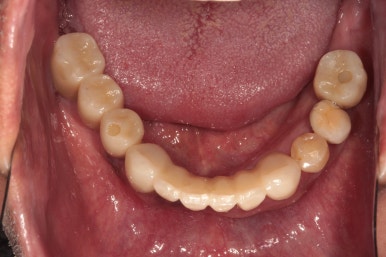

이루 말할 것 없이 깔끔하게 정리된 교합면 사진입니다.

사실 각 어금니마다 1개씩 임플란트가 더 식립되는 것이 28개의 치아를 재건하는데 필수적이나, 남성임에도 불구하고 턱이 아주 크진 않으셨기에 24개의 크라운만으로도 충분히 만족스러운 결과를 얻을 수 있었습니다.!!

다시봐도 지르코니아 크라운의 색상은 너무나 자연스러운 것 같아요... 상당히 완성도 있게 마무리 되었던 케이스였습니다. 개원 초기부터 믿고 잘 따라와주심에 감사드립니다 :)